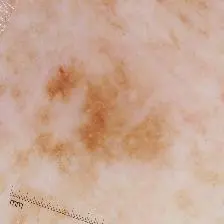

Illumination-based Transformations Improve Skin Lesion Segmentation in Dermoscopic Images

Kumar Abhishek, Ghassan Hamarneh, Mark S. Drew

ISIC Skin Image Analysis Workshop, IEEE International Conference on Computer Vision and Pattern Recognition (CVPR), 2020 We incorporate information from specific color bands, illumination invariant grayscale images, and shading-attenuated images obtained from RGB dermoscopic images of skin lesions to improve the lesion segmentation. [Abstract] [BibTeX] [Presentation Slides]

The semantic segmentation of skin lesions is an important and common initial task in the computer aided diagnosis of dermoscopic images. Although deep learning-based approaches have considerably improved the segmentation accuracy, there is still room for improvement by addressing the major challenges, such as variations in lesion shape, size, color and varying levels of contrast. In this work, we propose the first deep semantic segmentation framework for dermoscopic images which incorporates, along with the original RGB images, information extracted using the physics of skin illumination and imaging. In particular, we incorporate information from specific color bands, illumination invariant grayscale images, and shading-attenuated images. We evaluate our method on three datasets: the ISBI ISIC 2017 Skin Lesion Segmentation Challenge dataset, the DermoFit Image Library, and the PH2 dataset and observe improvements of 12.02%, 4.30%, and 8.86% respectively in the mean Jaccard index over a baseline model trained only with RGB images.